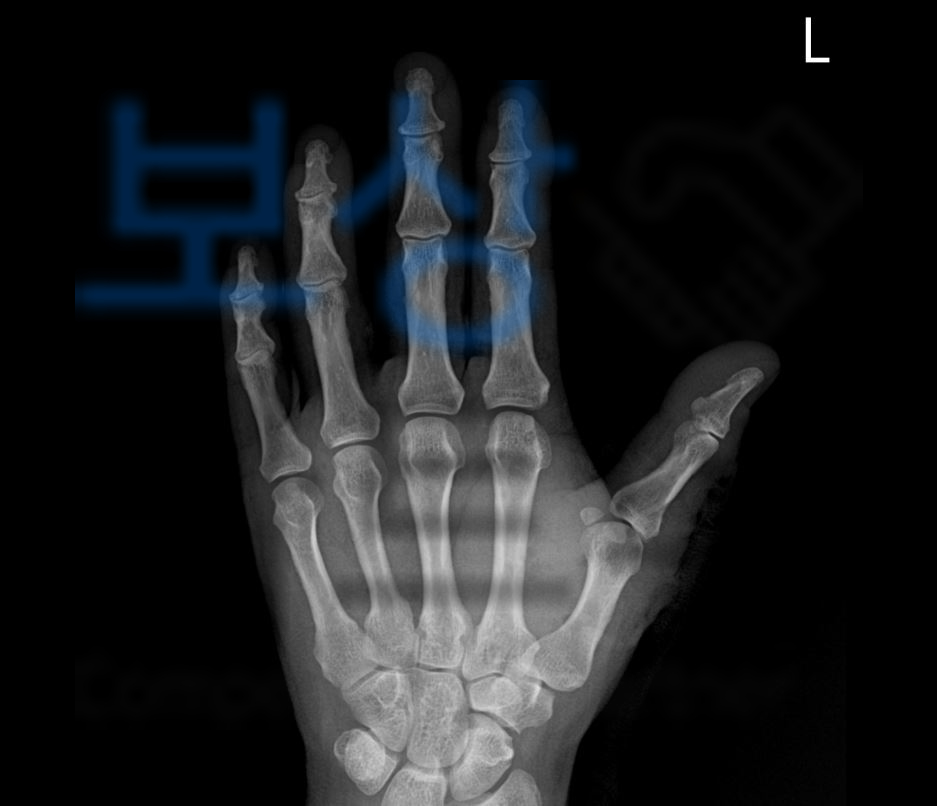

조@@님은 세탁소를 운영하셨는데요, 세탁소에서 글라인더로 작업을 하던 중 좌측 손등을 다치게 되어 급하게 119구급차를 타고 응급 진료를 보게 되었습니다.

뼈에는 다행히 절단되거나 큰 부상이 없었지만 손가락의 힘줄들이 끊어져 봉합술을 받으셔야 했습니다.

다행히 조@@님의 경우 3수지 즉 중지는 잘 움직이시는 듯 했으나 엄지손가락과 검지손가락이 운동범위에 제한이 있음이 보였죠.